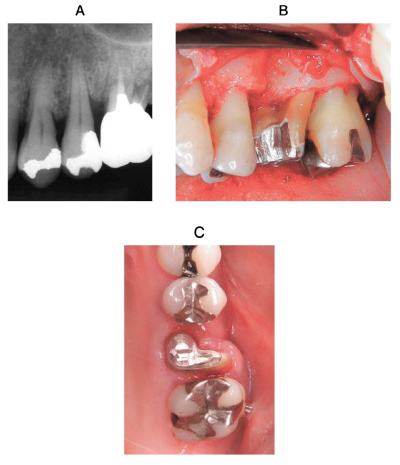

51歳の女性。上顎左側第一大臼歯部の違和感を主訴として来院した。歯周基本治療後の再評価の結果、歯周外科治療を行うこととした。術前のエックス線画像、術中の口腔内写真及び術後1か月で暫間被覆冠を除去したときの口腔内写真を別に示す。再評価時の歯周組織検査結果の一部を表に示す。

⎿6に対する処置の目的はどれか。1つ選べ。